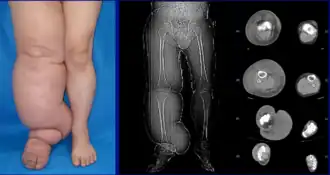

| Lower extremity lymphedema | |

The most common manifestation of lymphedema is soft tissue swelling (edema). As the disorder progresses, worsening edema and skin changes including discoloration, verrucous (wart-like) hyperplasia, hyperkeratosis, papillomatosis, dermal thickening, and ulcers may be seen. Additionally, there is increased risk of infection of the skin, known as erysipelas.

Lymphedema can occur in both the upper and lower extremities, and in some cases, the head and neck. Assessment of the extremities first begins with a visual inspection; color, presence of hair, visible veins, size and any sores or ulcerations are noted. Lack of hair may indicate an arterial circulation problem.[34] In cases of swelling, the extremities' circumference is measured over time for reference. In early stages of lymphedema, elevating the limb may reduce or eliminate the swelling. Palpation of the wrist or ankle can determine the degree of swelling; assessment includes a check of the pulses. The axillary or inguinal lymph nodes may be enlarged due to the swelling. Enlargement of the nodes lasting more than three weeks may indicate infection or other illnesses (such as sequela from breast cancer surgery) requiring further medical attention.[34]

Chronic venous stasis changes can mimic early lymphedema, but are more often bilateral and symmetric. Lipedema can also mimic lymphedema, however lipedema characteristically spares the feet beginning abruptly at the malleolus (ankle).[2] As a part of the initial work-up before diagnosing lymphedema, it may be necessary to exclude other potential causes of lower extremity swelling such as kidney failure, hypoalbuminemia, congestive heart-failure, protein-losing kidney disease, pulmonary hypertension, obesity, pregnancy and drug-induced edema.